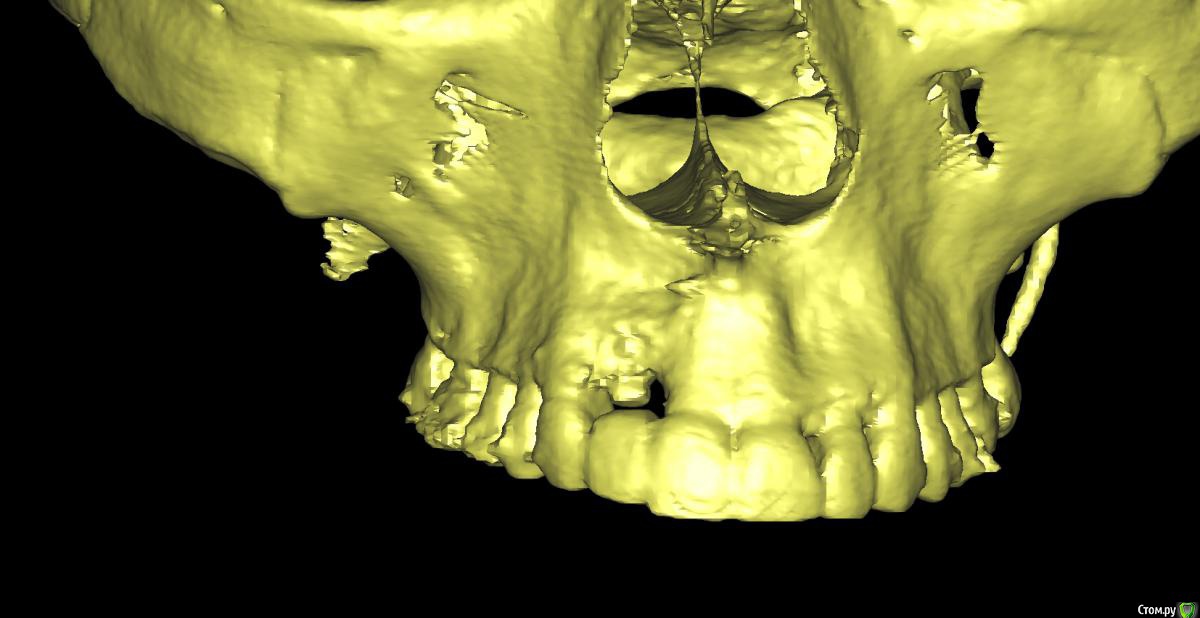

Irouil Опубликовано 1 сентября, 2019 Поделиться Опубликовано 1 сентября, 2019 Тут бы рентген смотреть Ссылка на комментарий

x4ex Опубликовано 1 сентября, 2019 Автор Поделиться Опубликовано 1 сентября, 2019 Тут бы рентген смотреть Ссылка на комментарий

Дмитрий М Опубликовано 3 сентября, 2019 Поделиться Опубликовано 3 сентября, 2019 12 - имплантат.так по снимку 12 - свой зуб! это резорбция у шейки или недозаглубили? Ссылка на комментарий

Dman Опубликовано 4 сентября, 2019 Поделиться Опубликовано 4 сентября, 2019 так по снимку 12 - свой зуб! 358.jpg это резорбция у шейки или недозаглубили? по всем снимкам 12- имплант, вы точно врач? опишите пожалуйста, каким именно? ну видно же, что на примерке ишемия, значит абатмент выталкивает мягкие ткани вестибулярно и коронально. Если делать пластику то трансплантат будет находиться и расти в том же направлении. Значит нужно сделать более вогнутый абатмент с переходом в коронку намного ниже, там, куда мы хотим сместить зенит. а для чего глушить? чтобы получить больше мягких тканей, потом сместить их вестибулярно, и получить необходимую высоту. Также будет возможность провести на раскрытии еще пластику и добавить ещею 1 Ссылка на комментарий